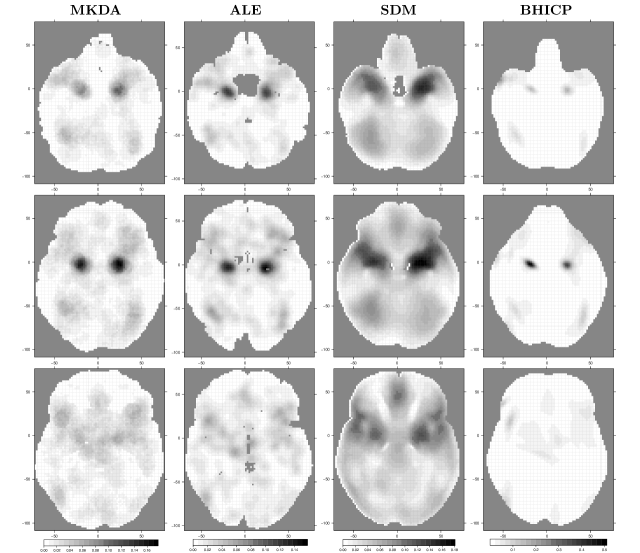

Figure 5 shows statistic images obtained from the four methods presented above, conditional on several values of the dimension. Note that for ALE, MKDA and SDM we show , and , respectively, whereas for the BHICP we show the voxel-wise posterior mean of the activation study intensity function, namely 111111Kang et al. (2011) note that singleton foci can also be viewed as activation centers since they come directly from the population centers.. We see that all of the methods provide qualitatively similar results. More specifically, the regions of the brain that are mostly engaged in emotion processing are the right and left amygdala (Fig. 5, top and middle row). This finding is consistent with previous analyses of the same dataset (Kober et al., 2008; Kang et al., 2011; Yue et al., 2012; Kang et al., 2014) as well as results of previous studies (Phelps and LeDoux, 2005; Costafreda et al., 2008). Other regions with moderately high values are the right and left cerebral cortex (Fig. 5, bottom row). For the BHICP, this pattern is only noticeable in the right cerebral cortex.

Interpretation. The meta-analysis of emotions suggests that the results obtained with model-based methods are qualitatively similar to those obtained with kernel-based methods. However, it is difficult to compare these results quantitatively as they have very different interpretations. At each voxel , the MKDA statistic represents the weighted proportion of studies that reported an activation within 10 mm of that given voxel. For the emotion dataset, the maximum value of , say , is and is located in the left amygdala. The ALE statistic estimates the probability that at least one of the foci closest to in each study is truly located at . We observe a maximum of for in our analysis. SDM uses ALE’s normal kernel but combines study maps as MKDA, hence interpretation is difficult. However, can be still viewed as a qualitative measure of foci clustering around . The maximum value for SDM is 0.181, and , the voxel where the maximum occurs, is also located near the left amygdala.

By lacking an explicit spatial model, kernel-based methods can not deliver, for example, spatial confidence intervals and an arbitrary kernel size parameter ( for MKDA and for ALE and SDM) must be set (though Eickhoff et al. (2009) offer heuristics). Typically, its value is specified based on previous studies rather than being estimated from the data, and it remains constant across the brain regardless of the amount of smoothing required in each region. However, a bad choice for the kernel size can potentially affect the results. For example, in the third column of Figure 5 we observe bigger clusters resulting from a choice for a larger kernel size than that used for MKDA and ALE. Yue et al. (2012) automatically choose the required amount of smoothing by introducing an extra smoothness parameters in their GMRF.